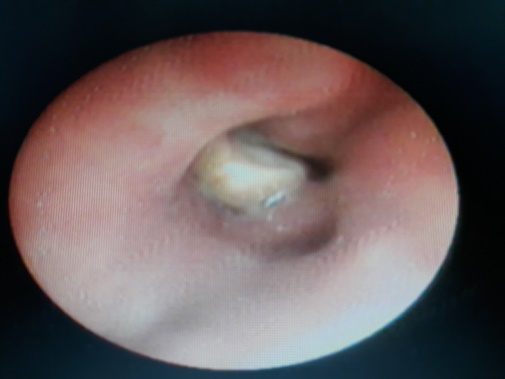

Hình ảnh nội soi cho thấy dị vật bị kẹt ở thùy dưới phổi phải của bà cụ 84 tuổi. |

Các bác sĩ đã lấy ra được 1 mảnh hạt sen dài 1,2cm bị mắc ở phế quản thùy dưới bên phải. Sau khi lấy dị vật, tình trạng hô hấp ở bệnh nhân nhanh chóng cải thiện. Hiện, bệnh tiếp xúc được, các dấu hiệu sinh tồn tạm ổn.

Mảnh hạt sen được các BS lấy ra ngoài có kích cỡ 0,5x0,5x1,2 cm. |